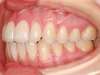

Cas N°6 : Description

Correction majeure des deux arcades dentaires liée à une mandibule rétrusive

Avant

Après